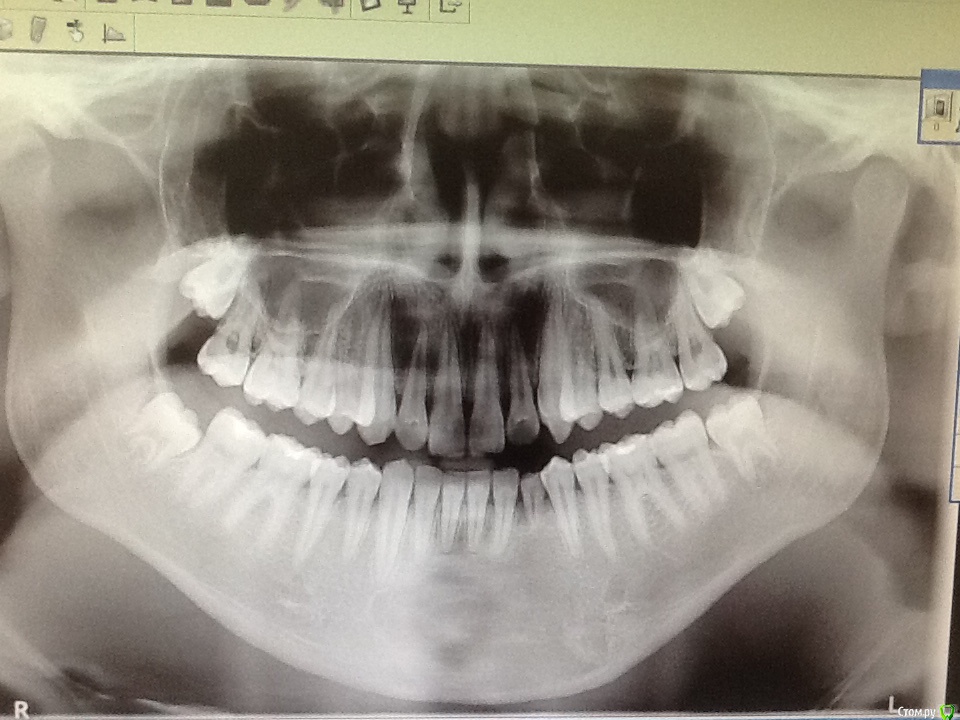

Л Ю С Я Опубликовано 5 сентября, 2016 Автор Поделиться Опубликовано 5 сентября, 2016 Если кому интересноСейчас парню 18 лет, термотест всех нижних резцов кроме 4.2 положительный, даже молочного клыка. 4.2 - решили наблюдать, перкуссия б. б, цвет не изменён. Надеюсь, что просто не восстановилась иннервация. Что скажите, когда можно делать имплант на место молочного резца? 2 Ссылка на комментарий

Чертков Александр Опубликовано 5 сентября, 2016 Поделиться Опубликовано 5 сентября, 2016 когда можно делать имплант на место молочного резца? КТ бы глянуть...и тогда ясно станет когда имплантат 1 Ссылка на комментарий